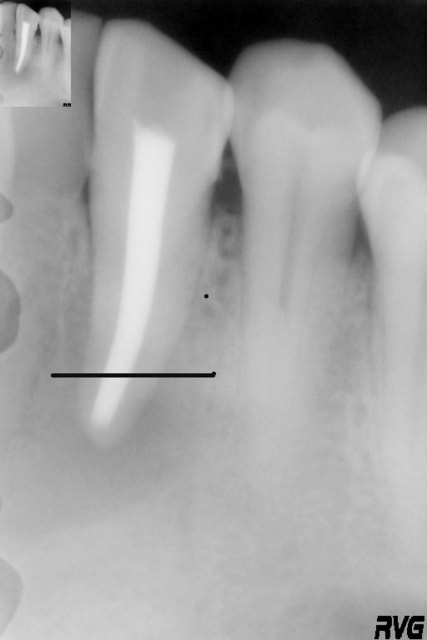

Un patient, 60 ans, présente une image apicale au niveau de 33, avec une fenestration ; tiers apical de la racine visible via la fenestration.

Ci joint, la radio de la 33 après le curetage par le stomato.

la radio pas top mais on l'a, radiologiquement correcte on dirait

Il s'agit juste d'une fenestration ou d'un apex extracortical ?